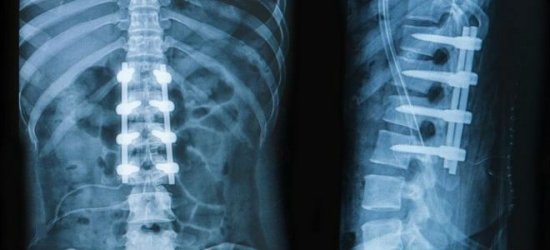

После обращения к травматологу потребуются лабораторные и аппаратные исследования, включающие в себя: анализ мочи и крови, рентгенографию, МРТ, электрокардиограмму . При лечении применяются как классические методы (фиксация и восстановление повреждённого позвонка), так и хирургические.